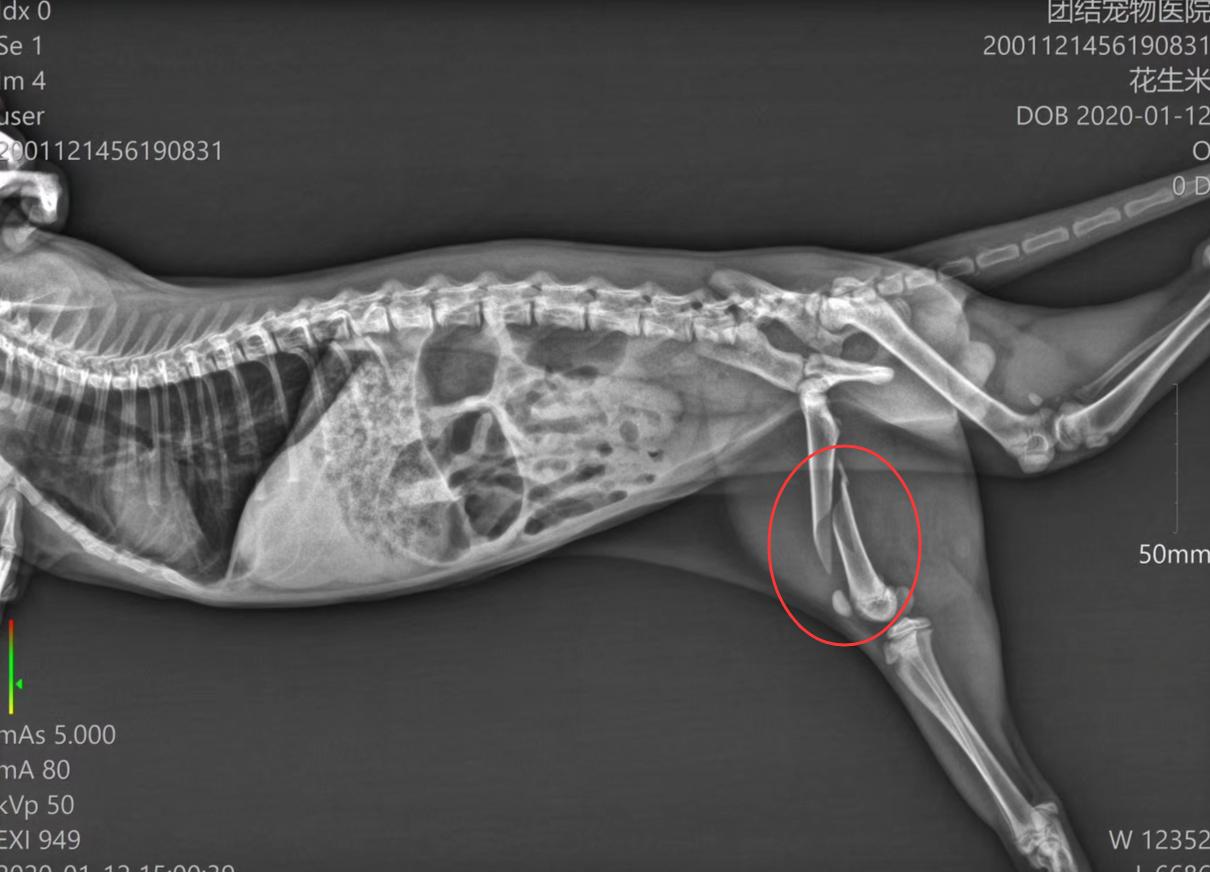

1月12号,重庆团结宠物医院高衡医生接诊了一只从16楼坠下的猫,这只猫是幸运的,首先这只猫还未成年,只有4.6斤,体重较轻,其次猫咪从16楼坠下后,掉到了1楼商铺的帆布遮雨棚上。

双重幸运下,经检查发现,这只猫咪虽然是从16楼坠下的,但只是一只腿骨折。

随后宠物医生对猫咪实施了紧急手术,为猫咪将骨折的骨头接上,并用钢板固定,目前猫咪依然在宠物医院住院。